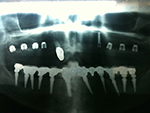

Implantation mit externem Sinuslift:

Implantation mit Knochenblock-Implantaten: